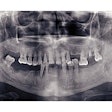

Patients who had surgery went from having an average of 15 caries lesions on tooth surfaces to 19.1. However, enamel lesions had decreased in those who had medical treatment, the researchers wrote.

As for deeper carious lesions in the dentine, patients had an average pretreatment initial value of 4.3 lesions. Two years after treatment, individuals in the surgery group had an average of 6.4 deeper lesions, while those in the medical treatment group had 4.9 lesions, according to the release.